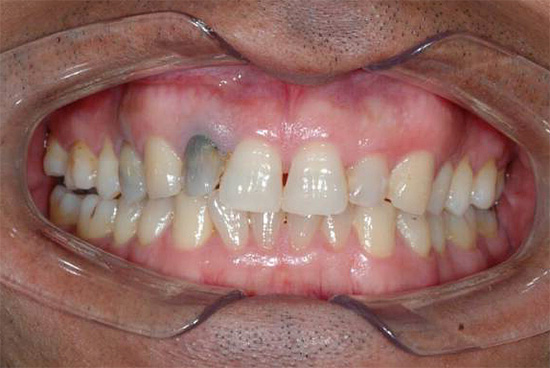

Se il messaggio cavità cariata con una camera pulpare, dove si trova il "nervo" collassante, buono e non ostacolato, quindi con la polipite cancrenosa non possono esserci sintomi di dolore. In tali casi, il paziente indica solo un cambiamento nel colore del dente - l'aspetto di una tinta grigiastra.

Foto di un dente con polmonite gangrenosa cronica: un'ombra grigia malsana è chiaramente visibile:

Quando si esamina un dente, la sua tinta grigia colpisce di solito in presenza di una cavità cariata che si estende in profondità nella bocca dei canali radicolari. Quando si sondano, si nota la presenza di una grande quantità di dentina ammorbidita cariata e la penetrazione profonda dall'estremità acuta della sonda nella bocca dei canali radicolari è spesso dolorosa, sebbene a volte si verifichi dolore quando viene uccisa una parte della polpa radicolare.